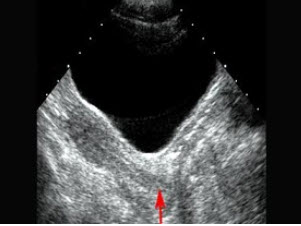

女性,出现腰痛并血尿3天,超声检查如图所示,该病例最可能诊断()

A.肾钙质沉积症

B.肾结石

C.肾内钙化灶

D.肾窦灶性纤维化

E.海绵肾

240、单项选择题

红色箭头所指部位是()

A.宫颈

B.阴道

C.子宫

D.宫体

E.以上都不是